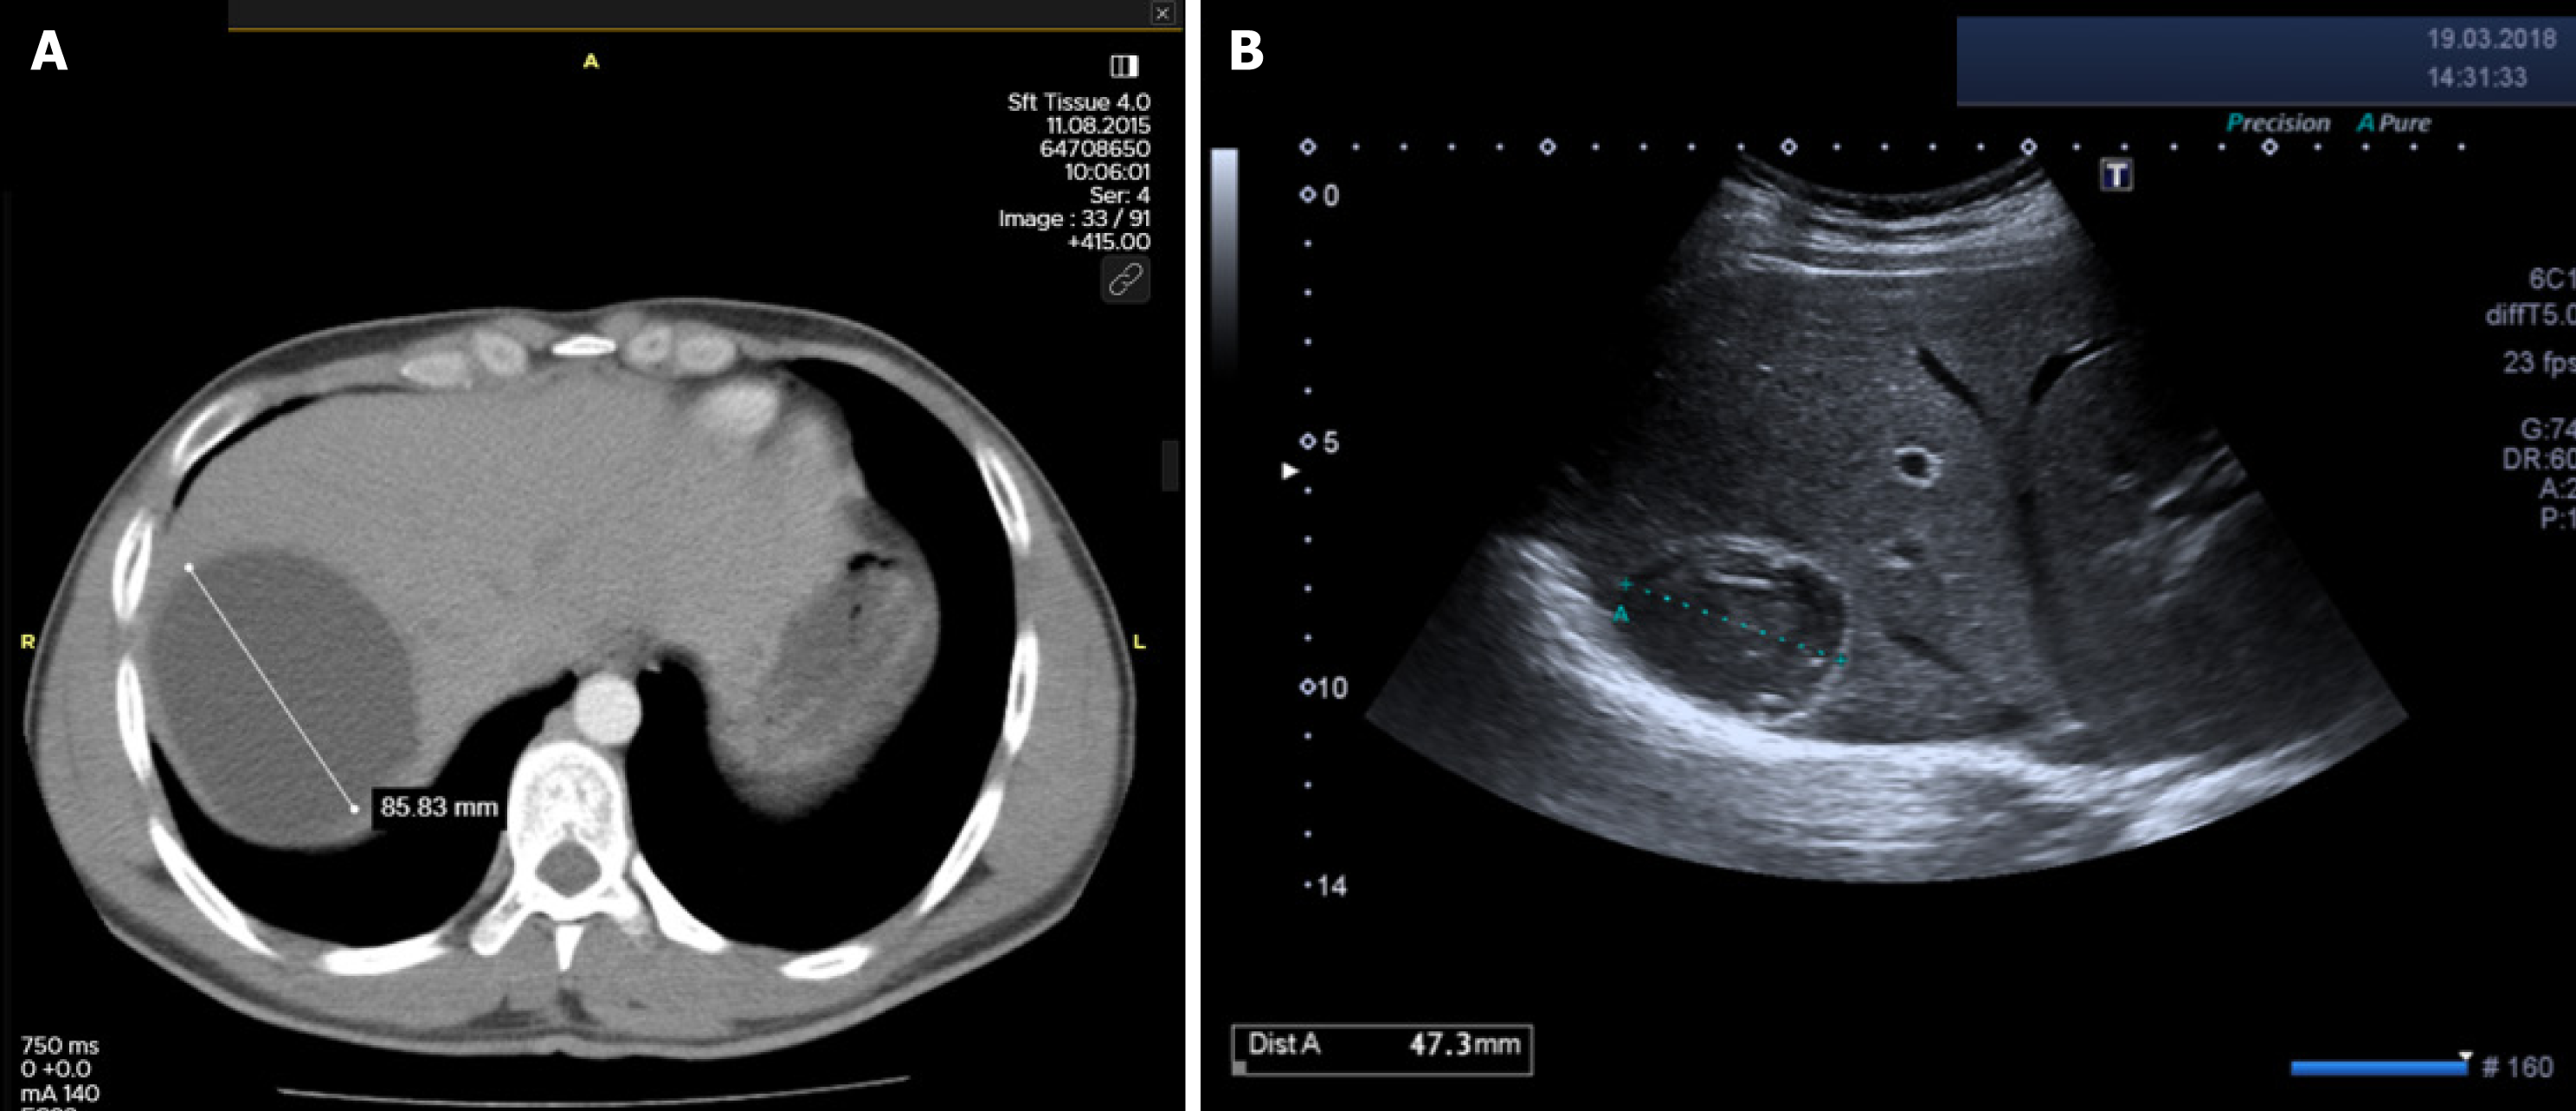

Table 2 summarizes the rates of major and minor complications according to treatment modality. The incidence of cystobiliary fistula (CBF) was comparable between the surgical and percutaneous groups (15.4% vs 16.8%; P = 0.651). However, recollection was significantly more frequent in the percutaneous group (4.7% vs 1.2%; P = 0.001), as was anaphylaxis (1.6% vs 0.3%; P = 0.041) (Figures 1 and 2). In contrast, true recurrence rates were low in both groups and did not differ significantly [surgical: 8/734 (1.1%) vs percutaneous: 4/255 (1.6%); P = 0.550]. Intraoperative organ injuries (diaphragm, liver, intestine) occurred in 2.7% of surgical patients (n = 20), but none were observed in the percutaneous group (P = 0.002). Minor complication rates were comparable between groups (23.4% vs 18.4%; P = 0.092). Postoperative pain was significantly more frequent in the surgical group (19.5% vs 11.0%; P = 0.002). Other minor complications such as fever, pleural effusion, and urticaria showed no significant differences between groups. Incisional or umbilical hernia occurred in 1.2% (n = 9) of surgical patients, while no hernias were observed in the percutaneous group (P = 0.067).

Anaphylaxis is a serious and potentially life-threatening complication that can occur during the treatment of CE. A systematic review of 5943 patients reported a fatal anaphylaxis rate of 0.03%, and a reversible anaphylactic reaction rate of 1.7%[18]. In another study focused exclusively on patients with giant cysts treated percutaneously, the rate of reversible anaphylaxis was 4.5%[19]. In our cohort, anaphylaxis occurred more frequently in percu